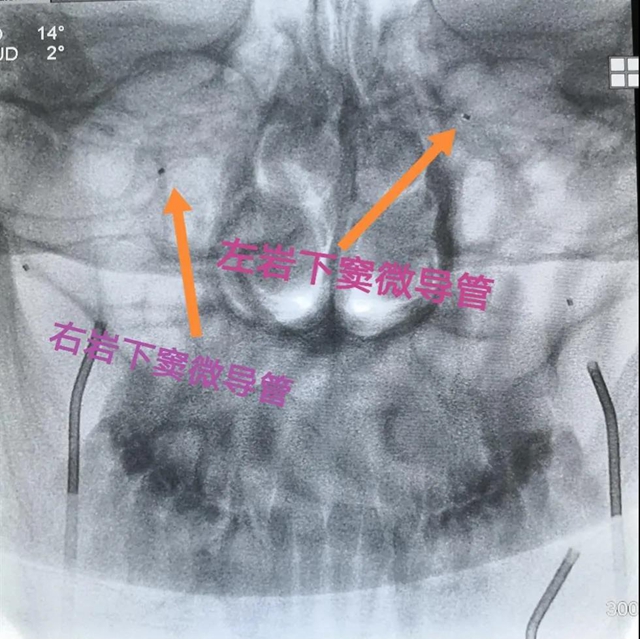

经过内分泌与代谢内科、神经外科、核医学科的多学科讨论,决定由介入医学部副主任黄昌仁教授、神经外科彭汤明博士和内分泌与代谢内科白雪主治医师开展双侧岩下窦静脉采血技术,通过对病灶经行定位,从而为患者能否进行垂体手术提供依据。

“这项技术需要采血的脑部血管非常细微,对神经介入技术要求很高,但此处采血,最能反应病人实际水平,对定位定性诊断和精准治疗有非常高的临床价值。”黄昌仁教授表示,通过多学科合作完成的这项技术,填补了神经外科神经介入的一项空白,更是多学科联合诊疗的成功范例。

最终,历时两个多小时,采血成功完成。根据取血结果,唐先生确诊患库欣病,再通过比较左右岩下窦静脉的激素含量,为指导后续手术进行精准诊断和治疗提供了依据。